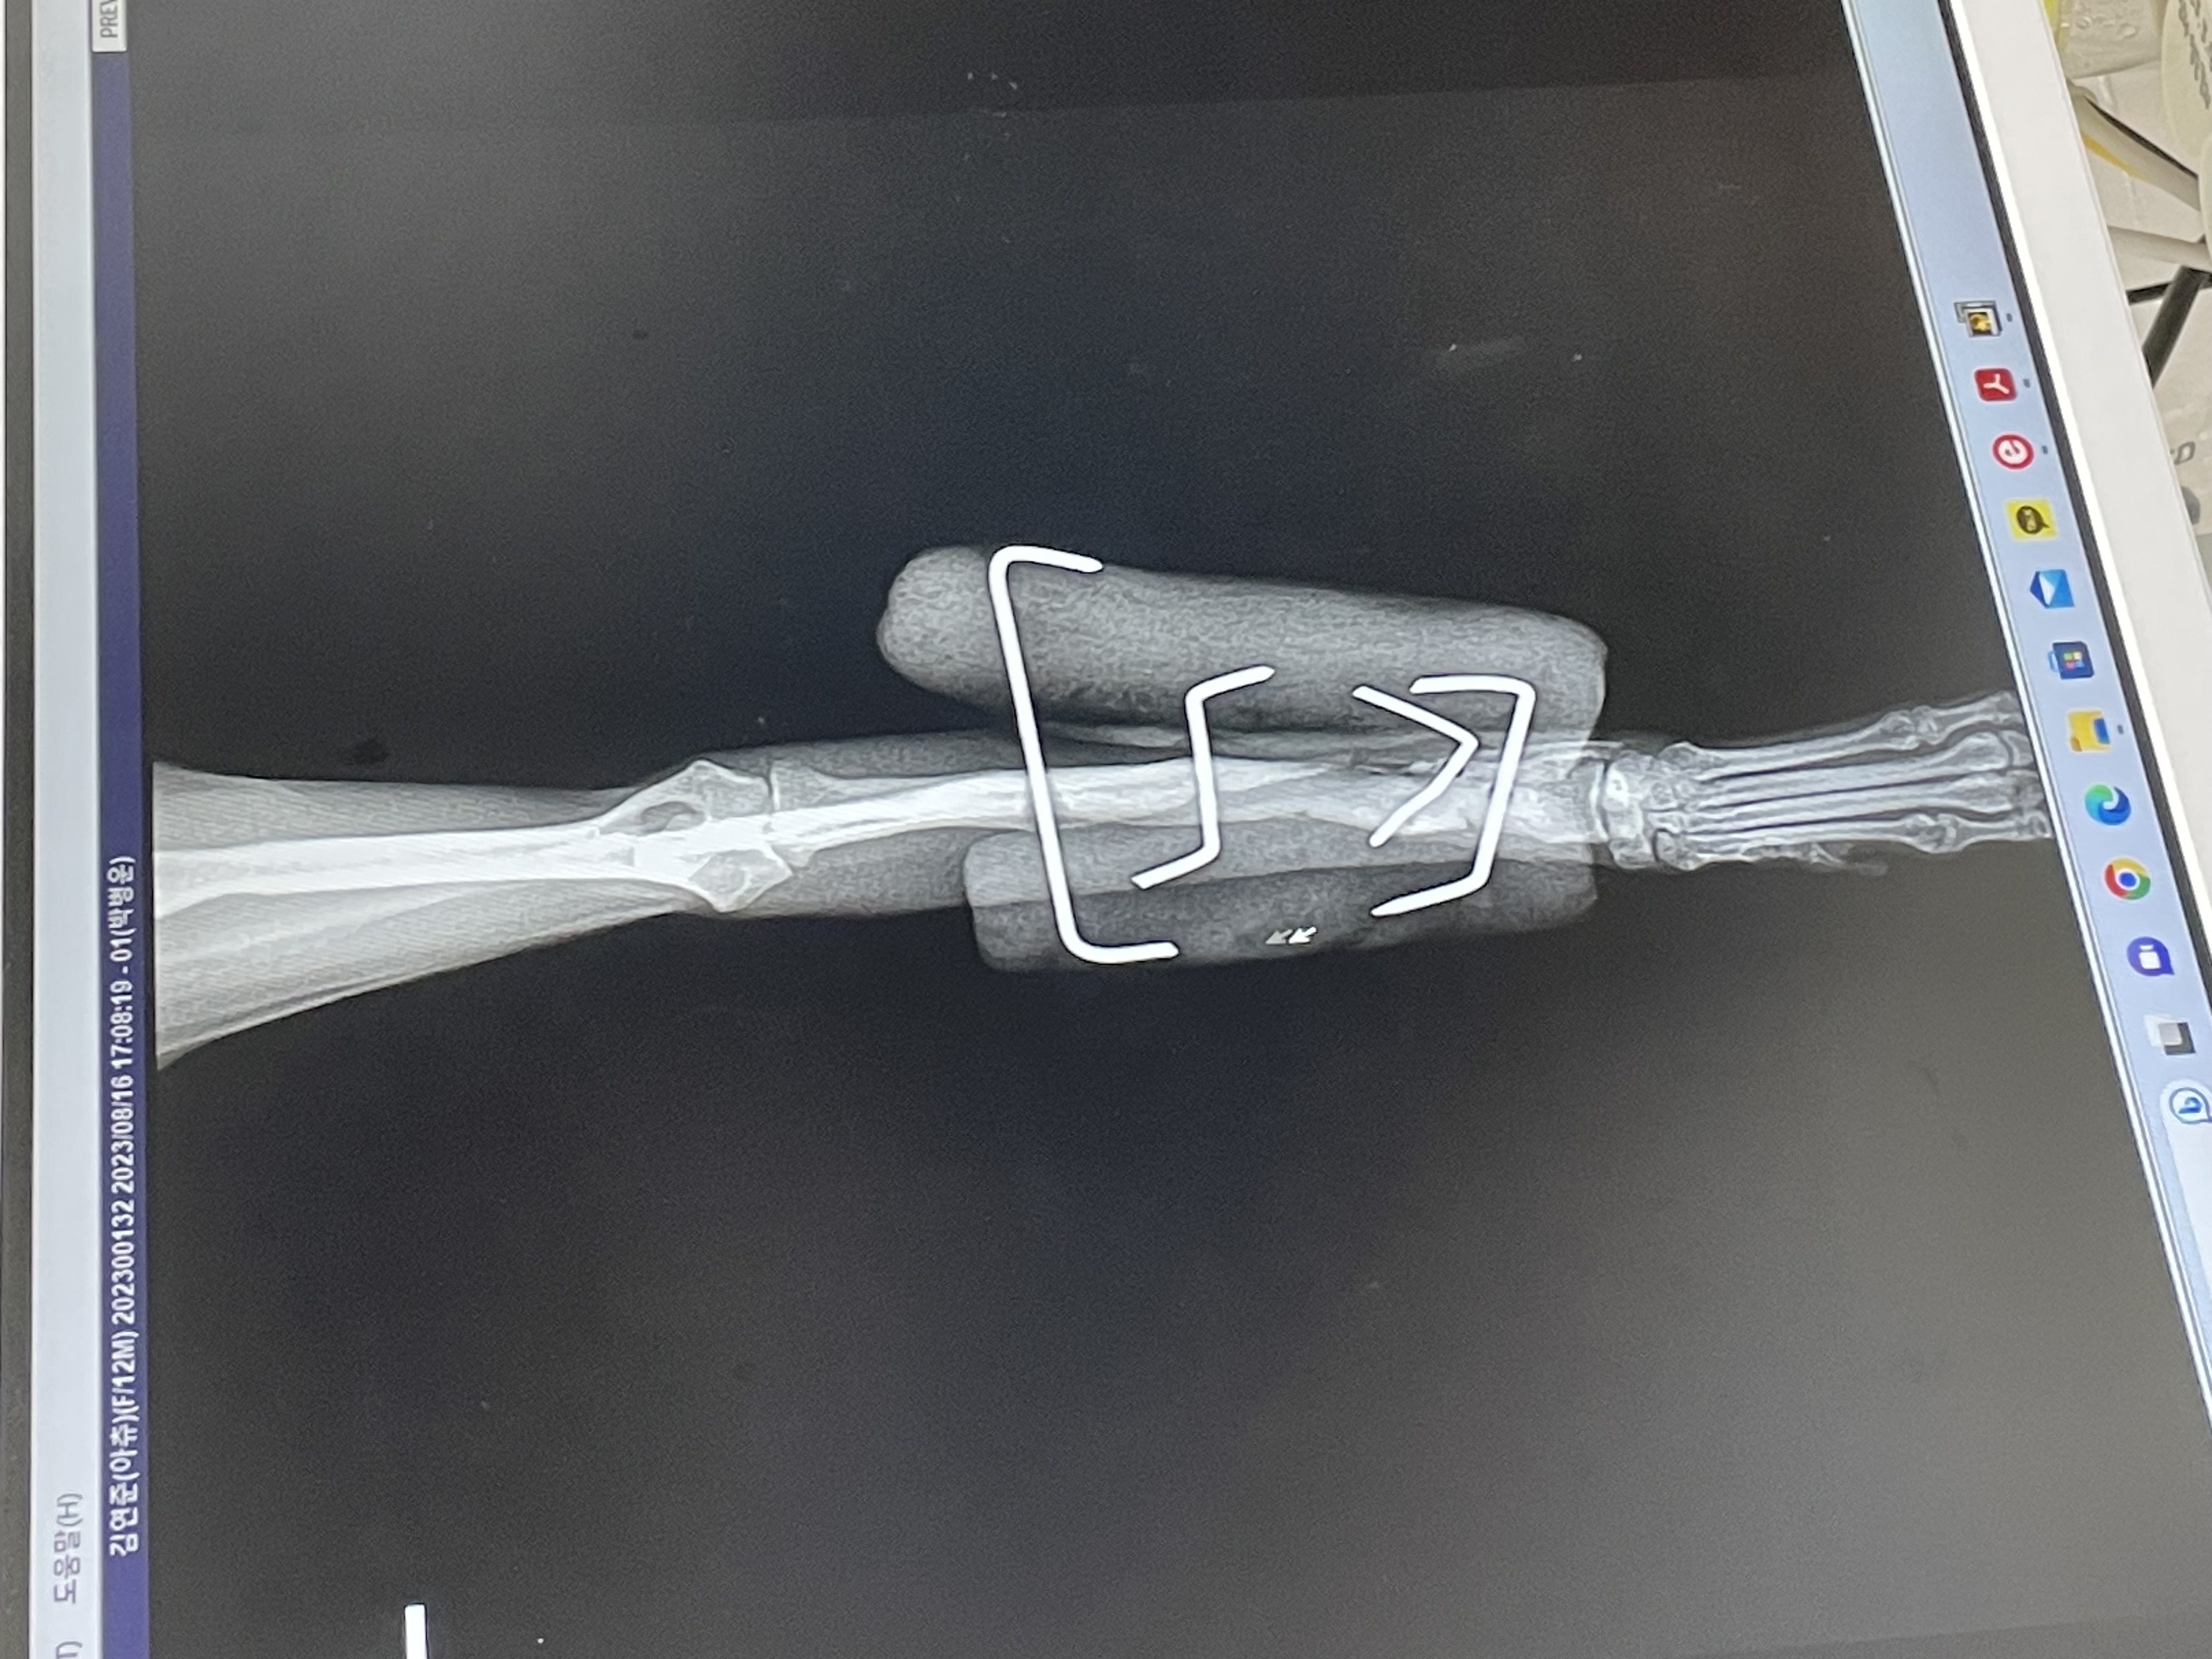

아츄 일주년 후기 올려요! 앗쮸는 6개월 전에 혼자 뛰어내려서 골절 이슈가 있었답니다 ^^..... 저도 츄도 더운 여름에 고생했는데 핳힣힣 (제 지갑도 껄껄... 허허) 드디어 다 나아서 외고정 장치도 지난달에 제거했고요, 장치 제거하고 거기 골수강이 차야 해서 지금 소프트 드레싱만 해둔 상태예여 ㅎㅅㅎ... 이제 포리랑 뛰어놀 수 있어서 신난 앗츄...

휴 다들 너무 안고 다니지 마시고... 소파 침대에 올리지 마시고 ㅎ...... 요척골 골절 조심하세요 ㅎ ,,, 저도 산책시키는데 큰 개가 막 짖어서 애 안있디가 얘가 놀래서 뛰어내린 것 허 허 허 허 허 omg